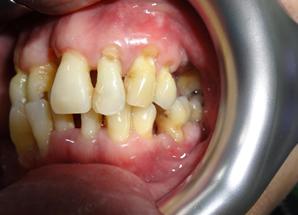

After the first therapy, there was total elimination of bad breathe and reduction in bleeding spot. Of course, I must complement his great effort in maintaining his oral hygiene. We repeated this procedure for another two times and review after 6 weeks, to allow gum healing. This is the result during review.

Gum appeared pinkish and healthy. No more gum bleeding, no more bad breathe, and teeth mobility was reduced. Clinical examination also showed great improvement. However, the lower front teeth are still loose, but no more bleeding.